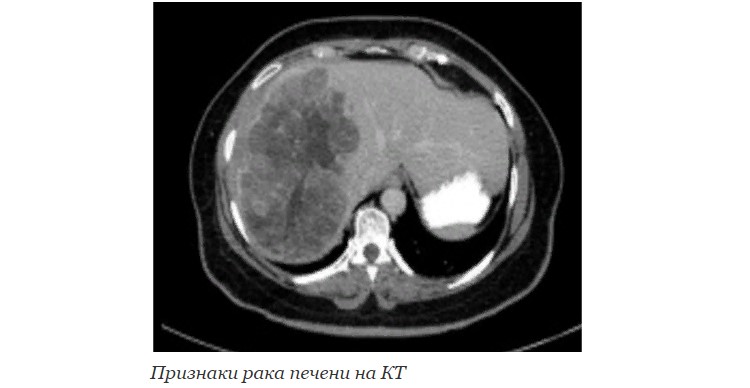

КТ, МРТ

Это методы компьютерной и магнитно-резонансной томографии. Позволяют получить высококачественные изображения структур брюшной полости и являются «золотым стандартом» диагностики опухолей с помощью тестов визуализации. Облегчают планирование оперативного доступа. Могут сочетаться с применением контрастных веществ – специальных препаратов, которые вводятся в организм для лучшего очерчивания границ патологических очагов.